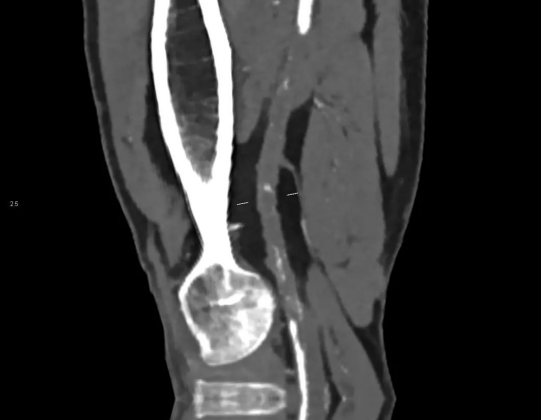

CPR可获得血管剖面信息,对于明确病变狭窄程度及支架内情况很有帮助。

患者男、75岁,行双下肢CTA后发现腹主动脉远端动脉瘤,累及双侧髂总动脉、右侧髂内动脉,并腔内附壁血栓形成,左侧髂外动脉节段性闭塞。